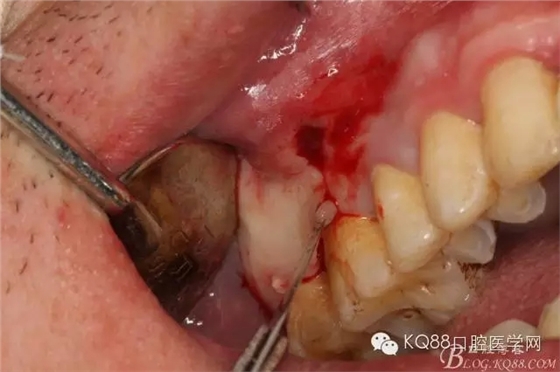

圖1.臨床檢查:16和17牙體組織正常、活力正常,其上方的前庭溝有一膿瘺,鑷子探查有大量膿性分泌物溢出。

圖6.局部浸潤麻醉下。在16的近中做垂直切口+遠(yuǎn)中齦溝內(nèi)及上頜結(jié)節(jié)水平切口

圖7.翻全厚瓣。發(fā)現(xiàn)17牙根方的骨質(zhì)破損,破損處有大量膿性血性分泌物溢出。

圖8.繼續(xù)翻瓣至上頜結(jié)節(jié)處,發(fā)現(xiàn)骨壁缺損有花生米大小,腔隙內(nèi)有大量肉芽組織。

圖9.清理缺損骨腔內(nèi)的膿性分泌物及炎性肉芽組織,目的是找到18在哪里,隱約可以看到18白色的小樣子喲。

圖10.去除了覆蓋在18牙冠表面的肉芽組織,暴露出18的部分牙冠。

圖11.千辛萬苦,總算看到18的合面了,唯一難做的就是牙齒在里面打轉(zhuǎn)轉(zhuǎn),固定不住牙,也無法夾持住它,好郁悶。

圖12.沒辦法,只能往16旁邊去了點(diǎn)骨質(zhì)。才把18它呼喚出來。病人說他的嘴巴快被拉扯了。

圖13.取出18后,出現(xiàn)的巨大空腔,上頜竇粘膜完全破損。